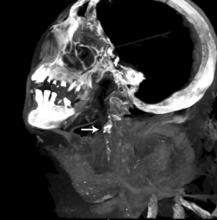

New research published in June issue of Global Heart (the journal of the World Heart Federation) show that there are no significant differences in the incidence or severity of atherosclerotic disease (narrowing of the arteries with fatty deposits) between ancient and modern people, showing that atherosclerosis is not just a disease of modern times. The journal included three articles [1,2,3] on the finding of the HORUS Study, which used CT scans from ancient mummies to compare arterial calcification caused by HORUS atherosclerosis.